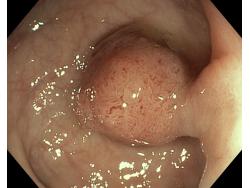

Polipy